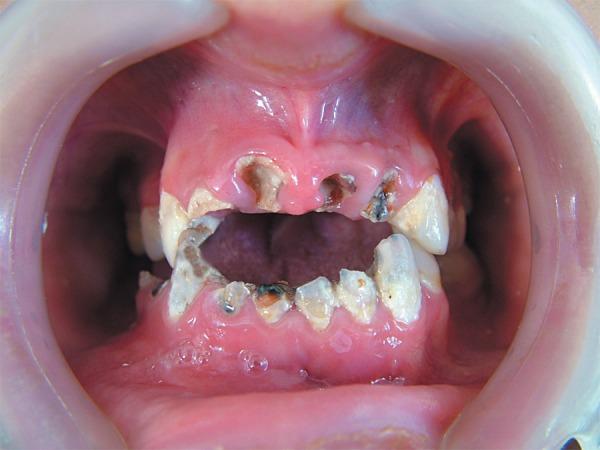

This paper reports the nonsurgical endodontic therapy using calcium hydroxide intracanal dressing and prosthetic treatment of 9 teeth with periapical lesions in a 16-year-old female patient. The periodontal treatment plan included oral hygiene instructions, mechanical debridement and gingivectomy in the maxillary incisors to improve gingival contouring. Root canal treatment was indicated for teeth 11-13, 21, 22, 42-45. After successive changes of a calcium hydroxide intracanal dressing during 6 weeks, the size of the periapical radiolucencies decreased and lesion remission occurred after root canal obturation. The endodontically treated teeth received a bondable polyethylene reinforcement fiber (Ribbond) in the prepared canal space and crown buildup was done with composite resin. Prosthetic rehabilitation was planned with single-unit metal-ceramic crowns and fixed partial dentures. Clinical and radiographic evaluation after 6 months showed successful results. The outcomes of this case showed that chronic periapical lesions can respond favorably to nonsurgical endodontic treatment in adolescent patients and that, with proper indication, polyethylene fibers can provide an effective conservative and esthetic option for reinforcing endodontically treated teeth undergoing prosthetic rehabilitation.

本文报告了一例 16 岁女性患者,9 颗有根尖病变的牙齿接受了非手术根管内氢氧化钙封药治疗和修复治疗。牙周治疗计划包括口腔卫生指导、上颌切牙的机械清创和牙龈切除术,以改善牙龈轮廓。11-13、21、22、42-45 号牙需要根管治疗。经过 6 周的多次更换氢氧化钙根管内封药,根尖的放射性透影区缩小,根管充填后病变缓解。经过根管治疗的牙齿在预备好的根管空间内使用可粘结的聚乙烯增强纤维(Ribbond),并用复合树脂进行牙冠修复。计划采用单冠金属陶瓷冠和固定局部义齿进行修复。6 个月后的临床和影像学评估显示治疗成功。该病例的结果表明,青少年患者的慢性根尖病变可以通过非手术根管治疗获得良好的效果,并且在适当的适应证下,聚乙烯纤维可以为接受修复治疗的根管治疗后牙齿提供一种有效的保守和美观选择。